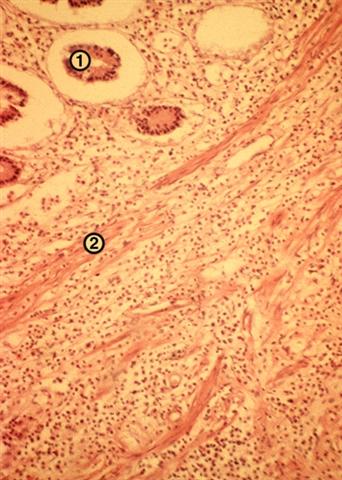

Рис. 1. Микропрепарат стенки червеобразного отростка при флегмонозном аппендиците: 1 — слизистая оболочка отростка, 2 — мышечная его оболочка, пронизанные густыми лейкоцитарными инфильтратами. Окраска гематоксилином и эозином; х 80.